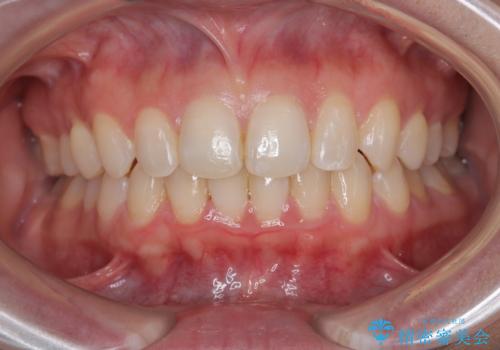

【モニター】インビザラインで気になるデコボコと八重歯をきれいに整える